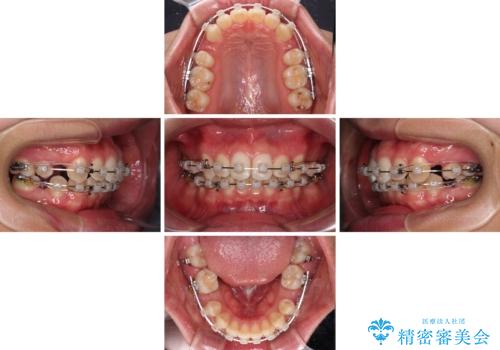

- 矯正装置

- クリアブラケット

- 治療期間

- 2年11ヶ月

- 治療回数

- 30回以上